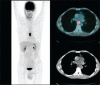

Accurate diagnosis and staging are essential for the optimal management of cancer patients. Positron emission tomography with 2-deoxy-2-[fluorine-18]fluoro-D-glucose integrated with computed tomography (18F-FDG PET/CT) has emerged as a powerful imaging tool for the detection of various cancers. The combined acquisition of PET and CT has synergistic advantages over PET or CT alone and minimizes their individual limitations. It is a valuable tool for staging and restaging of some tumors and has an important role in the detection of recurrence in asymptomatic patients with rising tumor marker levels and patients with negative or equivocal findings on conventional imaging techniques. It also allows for monitoring response to therapy and permitting timely modification of therapeutic regimens. In about 27% of the patients, the course of management is changed. This review provides guidance for oncologists/radiotherapists and clinical and surgical specialists on the use of 18F-FDG PET/CT in oncology.